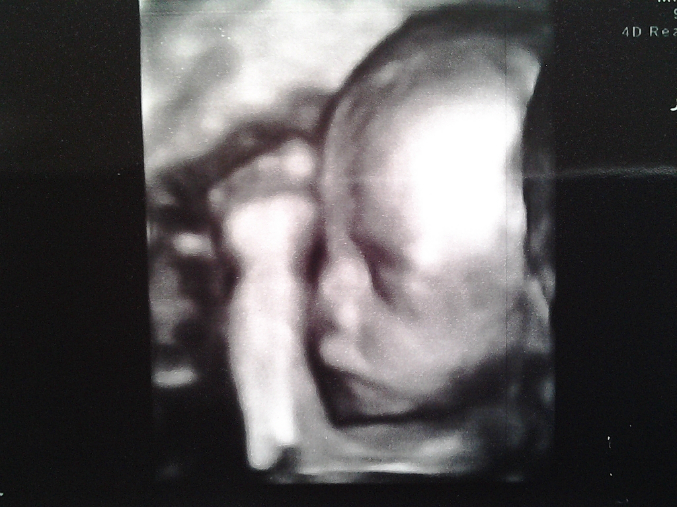

в клинике Здоровье( на пр. Космонавтов) , я там наблюдаюсь . УЗИ делала у Шульца( мне кажется, что у него почти весь наш город делает) Он УЗИст от Бога ., но сейчас он в отпуск ушел. 4д дороговато , но оно реально того стоит:)))